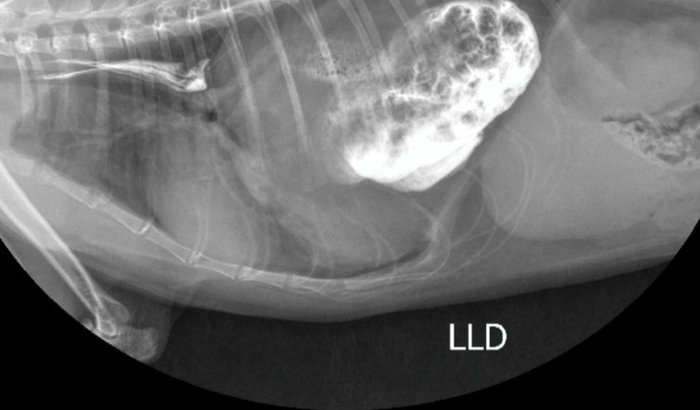

Hoje venho pedir ajuda com o coração apertado. A Milka tem apenas 10 meses de vida, e precisará fazer uma tomografia urgente devido sua dificuldade respiratória (controlada com medicação na veia a cada 2 dias). A suspeita inicial: pré diagnóstico de hérnia diafragmatica, mas para sabermos exatamente a gravidade da situação precisamos fazer a TOMOGRAFIA, que é o exame mais importante para descobrirmos exatamente, e seguir para os próximos passos, o exame custa R$1.118,00 e realizaremos na terça-feira: 18/11/2025.Esse mês, infelizmente, não consegui juntar esse valor, o que pra muitos seria possível, mas, exatamente nesse mês, passei por um momento muito difícil: meus gatos tiveram uma infecção urinária generalizada devido a ração, um atrás do outro. Fiz tudo o que pude ao extremo para todos, consultas, exames, medicações, suplementação, ração especial, e isso consumiu todo meu orçamento.